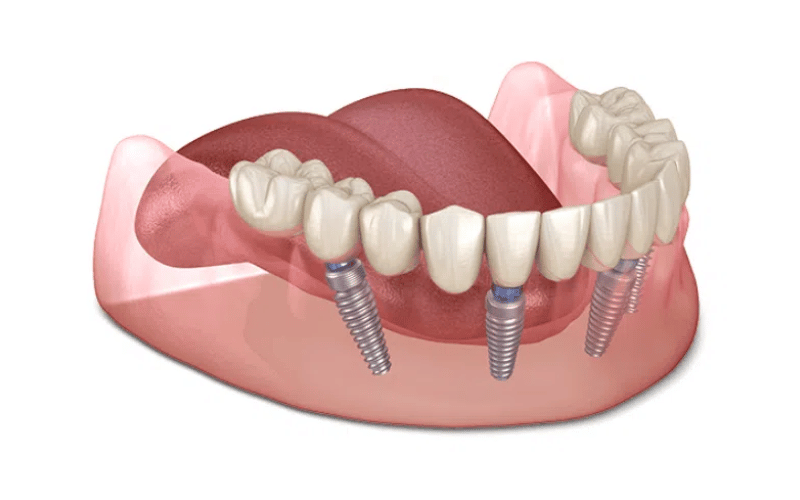

Trồng răng implant là một kỹ thuật tiên tiến trong nha khoa hiện đại, sử dụng một trụ titanium cấy trực tiếp vào trong xương hàm tại vị trí mất răng. Trụ này sẽ đóng vai trò như chân răng thật, sau một thời gian tích hợp với xương, bác sĩ sẽ gắn mão răng sứ lên trên thông qua một khớp nối gọi là abutment để hoàn thiện thân răng.

Khác với cầu răng sứ hay hàm tháo lắp, phương pháp implant phục hồi cả chân và thân răng, không xâm lấn răng kế cận, không gây tiêu xương và giúp duy trì khung xương hàm ổn định trong thời gian dài. Tuổi thọ của implant có thể lên đến 20–30 năm hoặc hơn nếu được chăm sóc đúng cách.

Trụ implant cần thời gian để tích hợp chắc chắn với xương, thường kéo dài từ 2–6 tháng tùy theo cơ địa và tình trạng xương hàm.

Bước 5: Gắn răng sứ lên trụ implant

Sau khi trụ ổn định, bác sĩ sẽ gắn abutment và mão sứ để hoàn thiện chiếc răng giả. Quá trình này yêu cầu độ chính xác cao về màu sắc, hình dạng và khớp cắn.